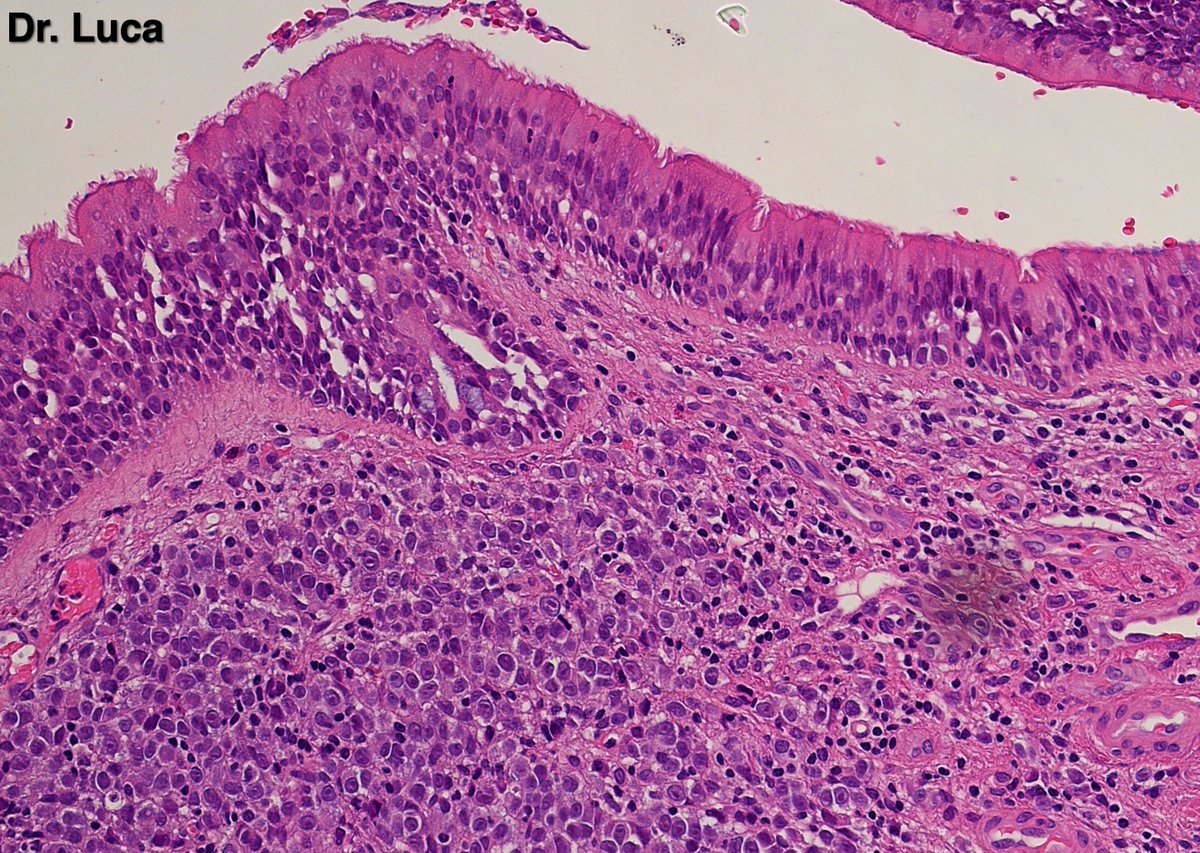

@Pathmath1 @SumantaDas_7 @PoloniaAntonio @ivanaspath @AnapathResident @bansar7 @goziemnweke @Teclis82 @Dr_Brian_Cox @DrBMcGinn @ariella8 @nusrat_xahra @DrRusella_Mirza @glinglerimek @kis_lorand @Venkateshgilly2 @DrBonita16 @DrPayelMondal @DrGeeONE @anjuthevirgo @niki_2389 @pepeheffernan @AngeloCassisa @NeoCrazee @TristanRutland7 Yes, it's a cancer with PNI...I show you the "superficial" layer of this cancer...what is the cancer? and what is the organ? #Pathology #GIpath #PathTwitter #PathResidents #pathboards